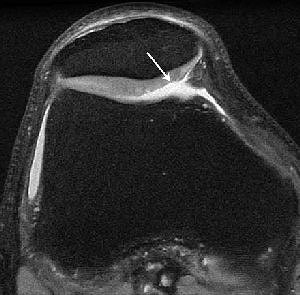

| Knee images in a 29-year-old man with knee pain. Axial proton-density image (TR/TE, 5,000/14; matrix, 512 x 384; slice thickness, 2 mm) acquired at 1.5-tesla shows fraying of lateral patella cartilage (arrow). Knee images in a 29-year-old man with knee pain. Axial proton-density image acquired at 3-tesla with identical parameters shows improved signal-to-noise ratio (SNR). Improved depiction of fraying of lateral patella cartilage (arrow) is seen at 3-tesla. Overall SNR at 3-tesla allows imaging at higher resolution. Gold GE, Suh B, Sawyer-Glover A, Beaulieu B, "Musculoskeletal MRI at 3.0 T: Initial Clinical Experience" (AJR 2004; 183:1479-1486). |